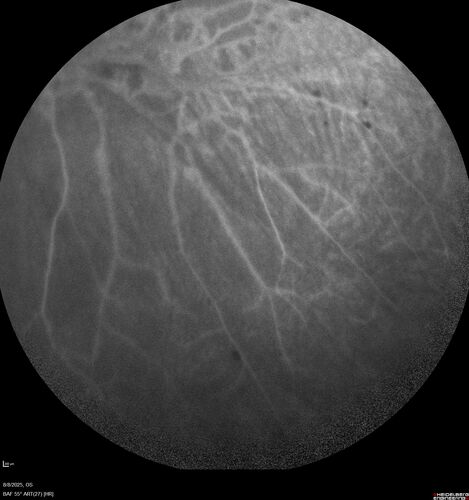

NPDR and Severe macular ischemia sudden vision loss

60 year old female with sudden vision loss OD 1 week ago. VA 20/63, 20/200. OCT-A and FA shows severe macular ischemia OU